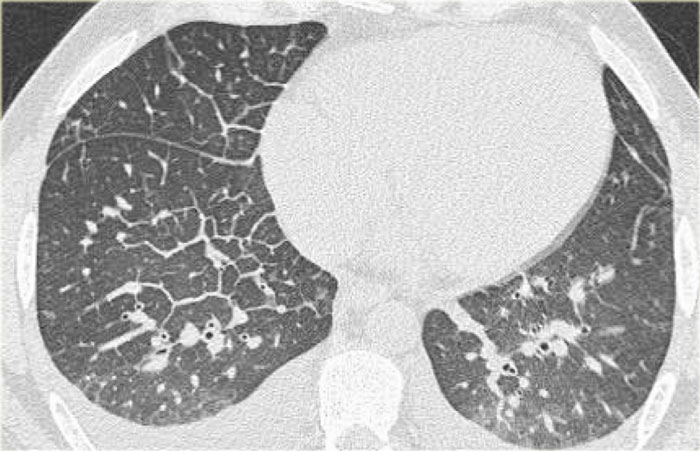

CT will also demonstrate signs of congestive heart failure.

On the image on the left notice the following:

• Thickened septal lines due to interstitial edema

• Subtle ground glass opacity in the dependent part of the lungs (HU difference of 100-150 between the dependent and non-dependent part of the lung).

• Bilateral pleural fluid.

In a patient with a known malignancy lymphangitic carcinomatosis would be high in the differential diagnostic list.